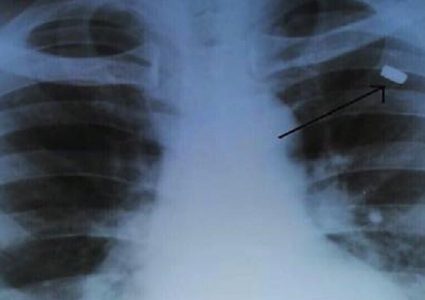

حمل الروسي ألكسي ألفيورف، رصاصة في عينه لمدة 17عاما، والتي تعود لسنوات الدراسة. وحسب موقع" غوفوريت موسكفا" الروسي، فإن الحادث يعود إلى أيام الدراسة، حيث ...